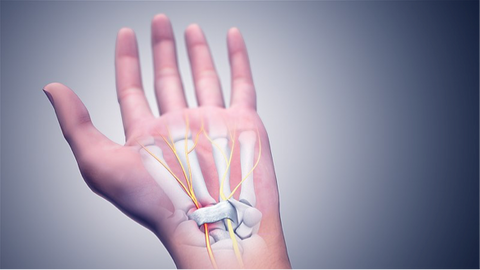

The most common overuse injury seen in the hands is tendinitis. Tendinitis causes inflammation (swelling) of the tendons that attach muscles to bones. Tendinitis can lead to significant pain, thus reducing the function of the wrists and hands. The image below shows just a fraction of the tendons of the wrists and hands. You can imagine how damage to any of these tendons will lead to less use of the wrists and hands, gradually causing them to become weaker and weaker.

Tendons of the hand